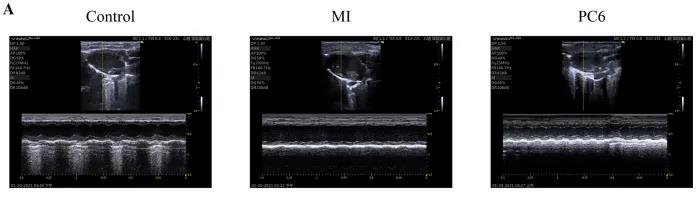

成年雄性C57BL/6雄性小鼠隨機分為對照組、MI組和PC6組。MI組小鼠為通過結扎冠狀動脈左前降支(LAD)形成MI模型,PC6組在造模完成后,針刺內關穴治療5天后取材。經胸超聲心動圖評估MI手術前后小鼠心功能情況,并進行血清心肌酶和炎癥細胞因子的測定,之后三組樣本各取3個重復,共9個樣本進行ONT全長轉錄組測序。

為了探討針刺PC6穴對心肌損傷的影響,作者首先評估了心功能和梗死面積。超聲心動圖結果顯示MI組的EF(ejection fraction)和FS(fractional shortening)均較對照組明顯降低。PC6穴位治療后,EF和FS均增加。針刺治療5天后, 采用TTC染色檢測梗死面積。結果顯示,針刺治療顯著減小心肌損傷的大小。采用ELISA法測定反映急性心肌損傷的心肌特異性血清酶,包括心肌肌鈣蛋白T (cTnT)和心肌肌鈣蛋白I (cTnI)的水平。結果表明,心肌梗死術后cTnT和cTnI水平升高,針刺可顯著降低血清酶水平。